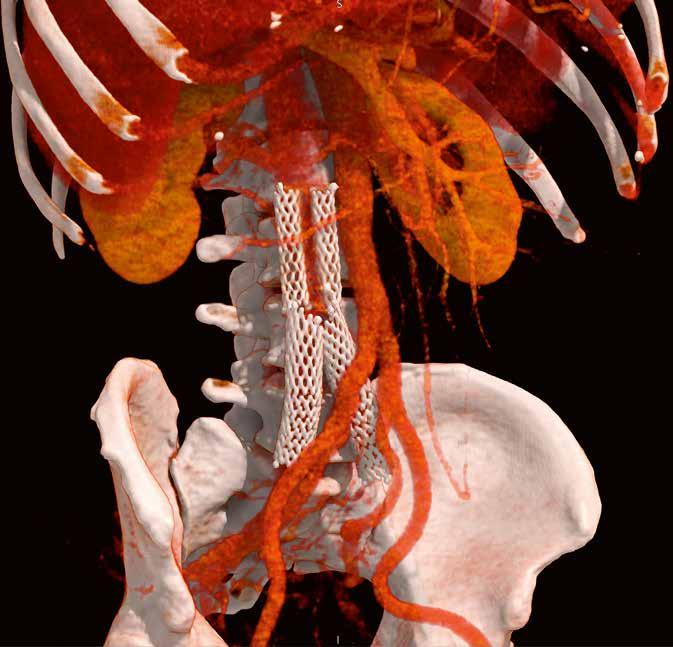

39-jähriger Pat., Z. n. venöser Stent-Anlage bei postthrombotischem Syndrom. Erbitte Gefäßdarstellung zur Stent-Revision. Aquilion PRISM (AiCE) DLP: 833,9 mGy*cm vs. 569,1 mGy*cm Aquilion PRIME (AIDR 3D)